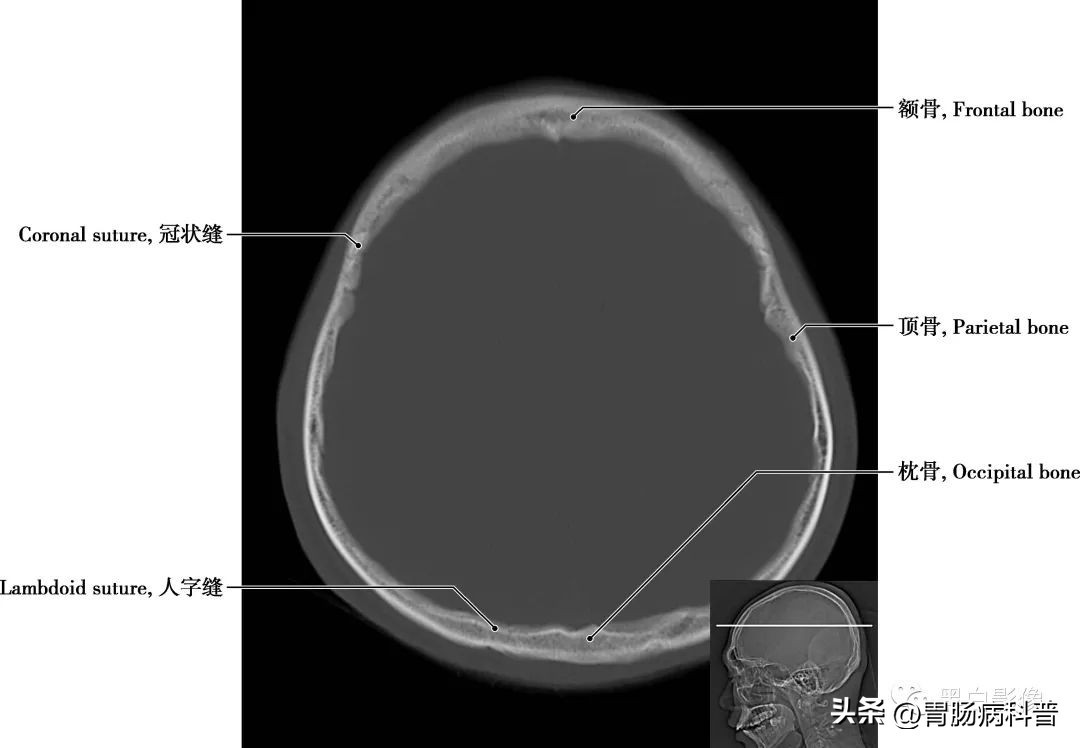

图1-2-3 经中央旁小叶上部轴位切面

额骨 位于前额处,分为三部分,即额鳞,大而垂直,在前额;眶部,环状或水平,对眼眶顶部和鼻腔的形成至关重要;鼻部,与鼻骨和颌骨的额突在鼻根部形成关节,其前与筛骨和鼻骨相连,后通过冠状缝与顶骨相连